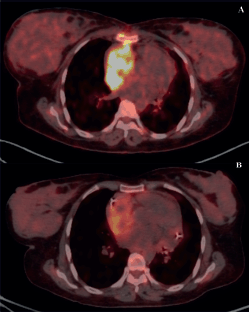

Figure 4. PET scans of a patient with locally advanced/unresectable cardiac angiosarcoma (a): Before chemotherapy and (b): After 5 cycles of single-agent gemcitabine.

Of 9 evaluable responses (both as first line and subsequent lines) among palliative setting 5 (55.5%) were PR (Figures 3c and 4), 3 (33.3%) were SD and 1 (11.2%) progression. Median progression-free survival (PFS) with systemic therapy was 5.4 months (95% CI: 0β13.7) (Figure 5a). Median overall survival (OS) was 1.2 months (those who did not receive systemic therapy) versus 19.2 months (those who received systemic therapy) (95% CI: 0β42.2) (Figure 5b). The median OS for the entire cohort was 5.1 months (95% CI: 0.2β10.0) (Figure 5c).